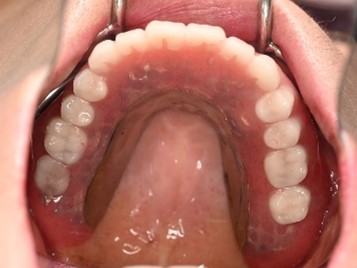

【義歯を装着したところ】

【義歯を外したところ】

【マグネット式総入れ歯】

上顎

下顎